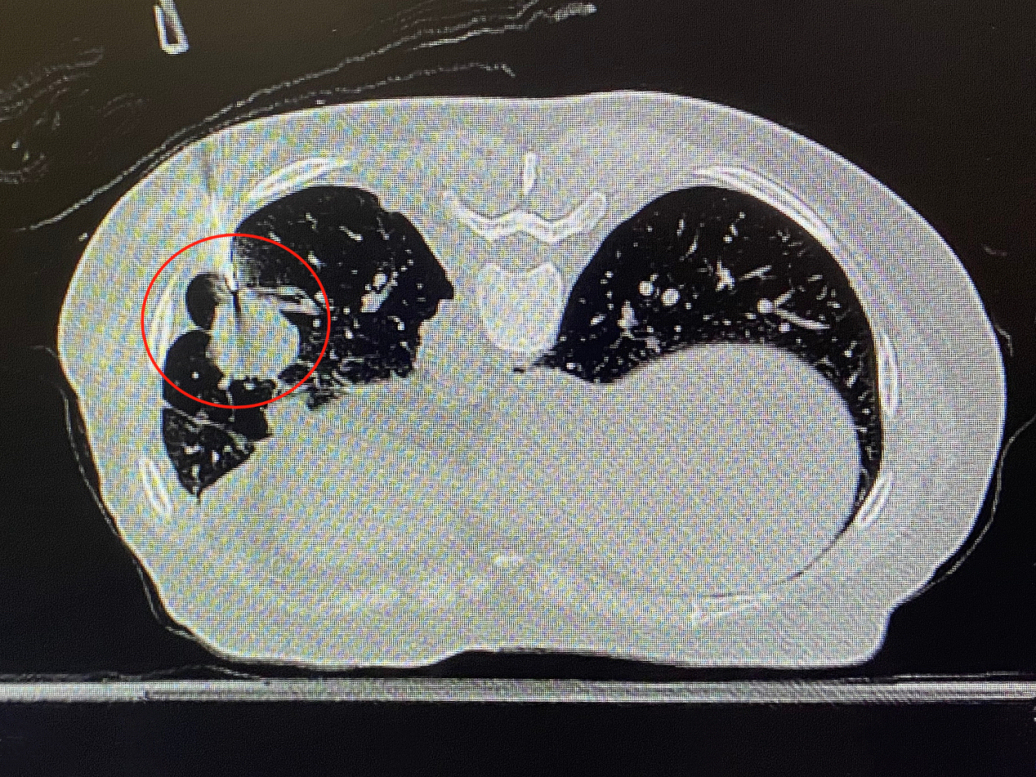

CT复扫确认穿刺针到达规划点(红圈内)

手术当天,彭医生首先根据术前影像,采用俯卧位,体位固定垫固定患者牢靠,以确保术中的稳定性。随后,将患者的CT扫描影像传输至RC120导航定位机器人系统,迅速对患者的肺部进行了二维图像与三维模型的重建。

在RC120导航定位机器人的辅助下,整个手术过程非常顺利,无需调针,实现了“一针到位”的精准定位,且整个过程仅耗时10分钟,在穿刺过程中华敏状态也非常好,未出现任何并发症。